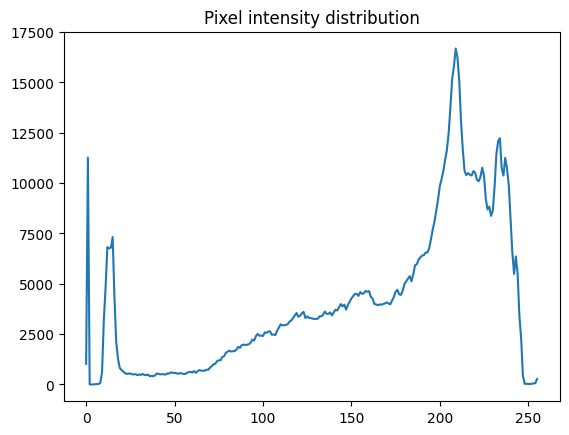

1. 获取有关您正在处理的原始 X 射线图像中像素值的一些基本统计信息:

print("X 射线图像的数据类型是:", xray_image.dtype)

print("最小像素值是:", np.min(xray_image))

print("最大像素值是:", np.max(xray_image))

print("平均像素值是:", np.mean(xray_image))

print("中位数像素值是:", np.median(xray_image))

X 射线图像的数据类型是: uint8

最小像素值是: 0

最大像素值是: 255

平均像素值是: 172.52233219146729

中位数像素值是: 195.0

2. 数组的数据类型是 uint8,最小/最大值的结果表明 X 射线中使用了所有 256 种颜色(从 0 到 255)。让我们使用 ndimage.histogram() 和 Matplotlib 可视化原始原始 X 射线图像的 像素强度分布:

pixel_intensity_distribution = ndimage.histogram(

xray_image, min=np.min(xray_image), max=np.max(xray_image), bins=256

)

plt.plot(pixel_intensity_distribution)

plt.title("像素强度分布")

plt.show()

正如像素强度分布所示,有许多低(约在 0 到 20 之间)和非常高(约在 200 到 240 之间)的像素值。